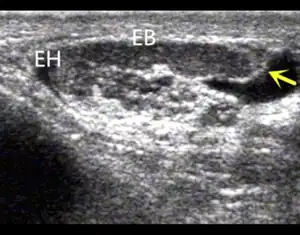

EP shows the thin and short EB-epididymal body, and absence of ET-epididymal tail (CAVD is associated with SV and EP anomalies).

Scrotal ultrasonography and transrectal ultrasonography (TRUS) are useful in detecting uni- or bilateral CAVD, which may be associated with visible abnormalities or agenesis of the epididymis, seminal vesicles or kidneys.[10]